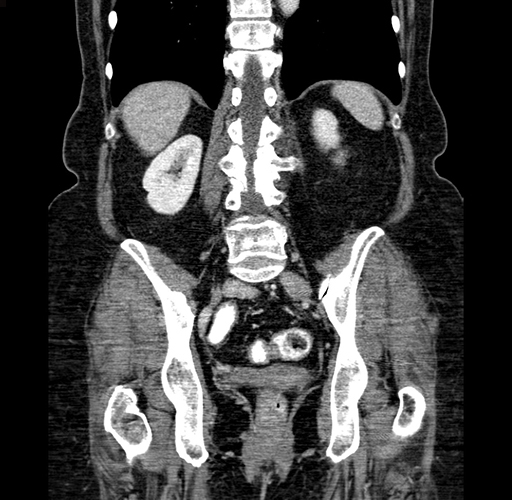

Pre-Chemo: Coronal Venous